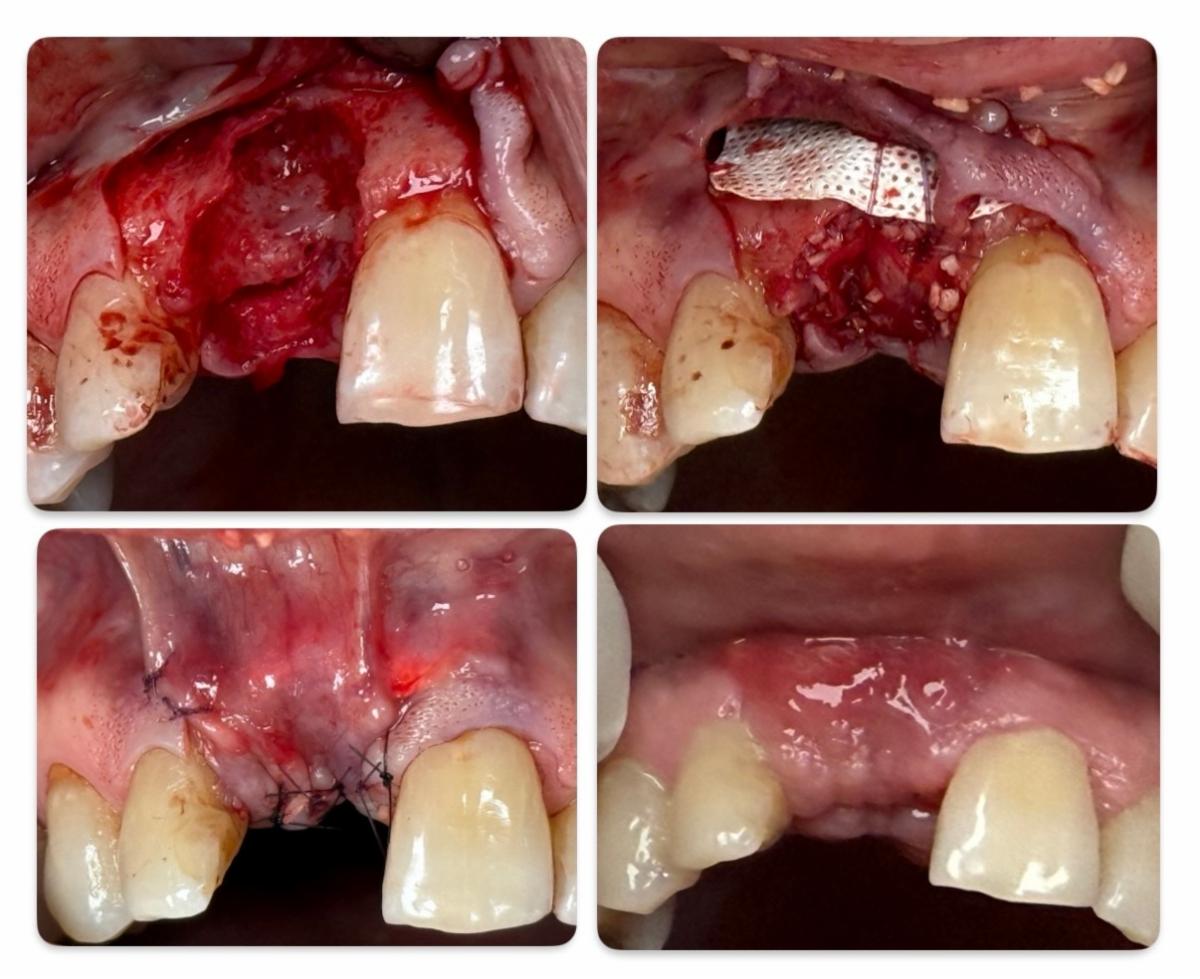

Case 1: Immediate Grafting with Primary Closure

This case involved a maxillary central incisor with a large facial wall defect. Tooth #8 was extracted and

immediately grafted. Tension-free primary closure was achieved through a coronally advanced flap.

While the bone graft was well-contained, the flap design led to:

- Shortening of the vestibule

- Coronal displacement of the mucogingival junction

These changes disrupted the natural soft tissue contours and may present esthetic challenges for future implant

restoration. Proper recognition and management of these complications are essential and may require additional

soft tissue procedures.